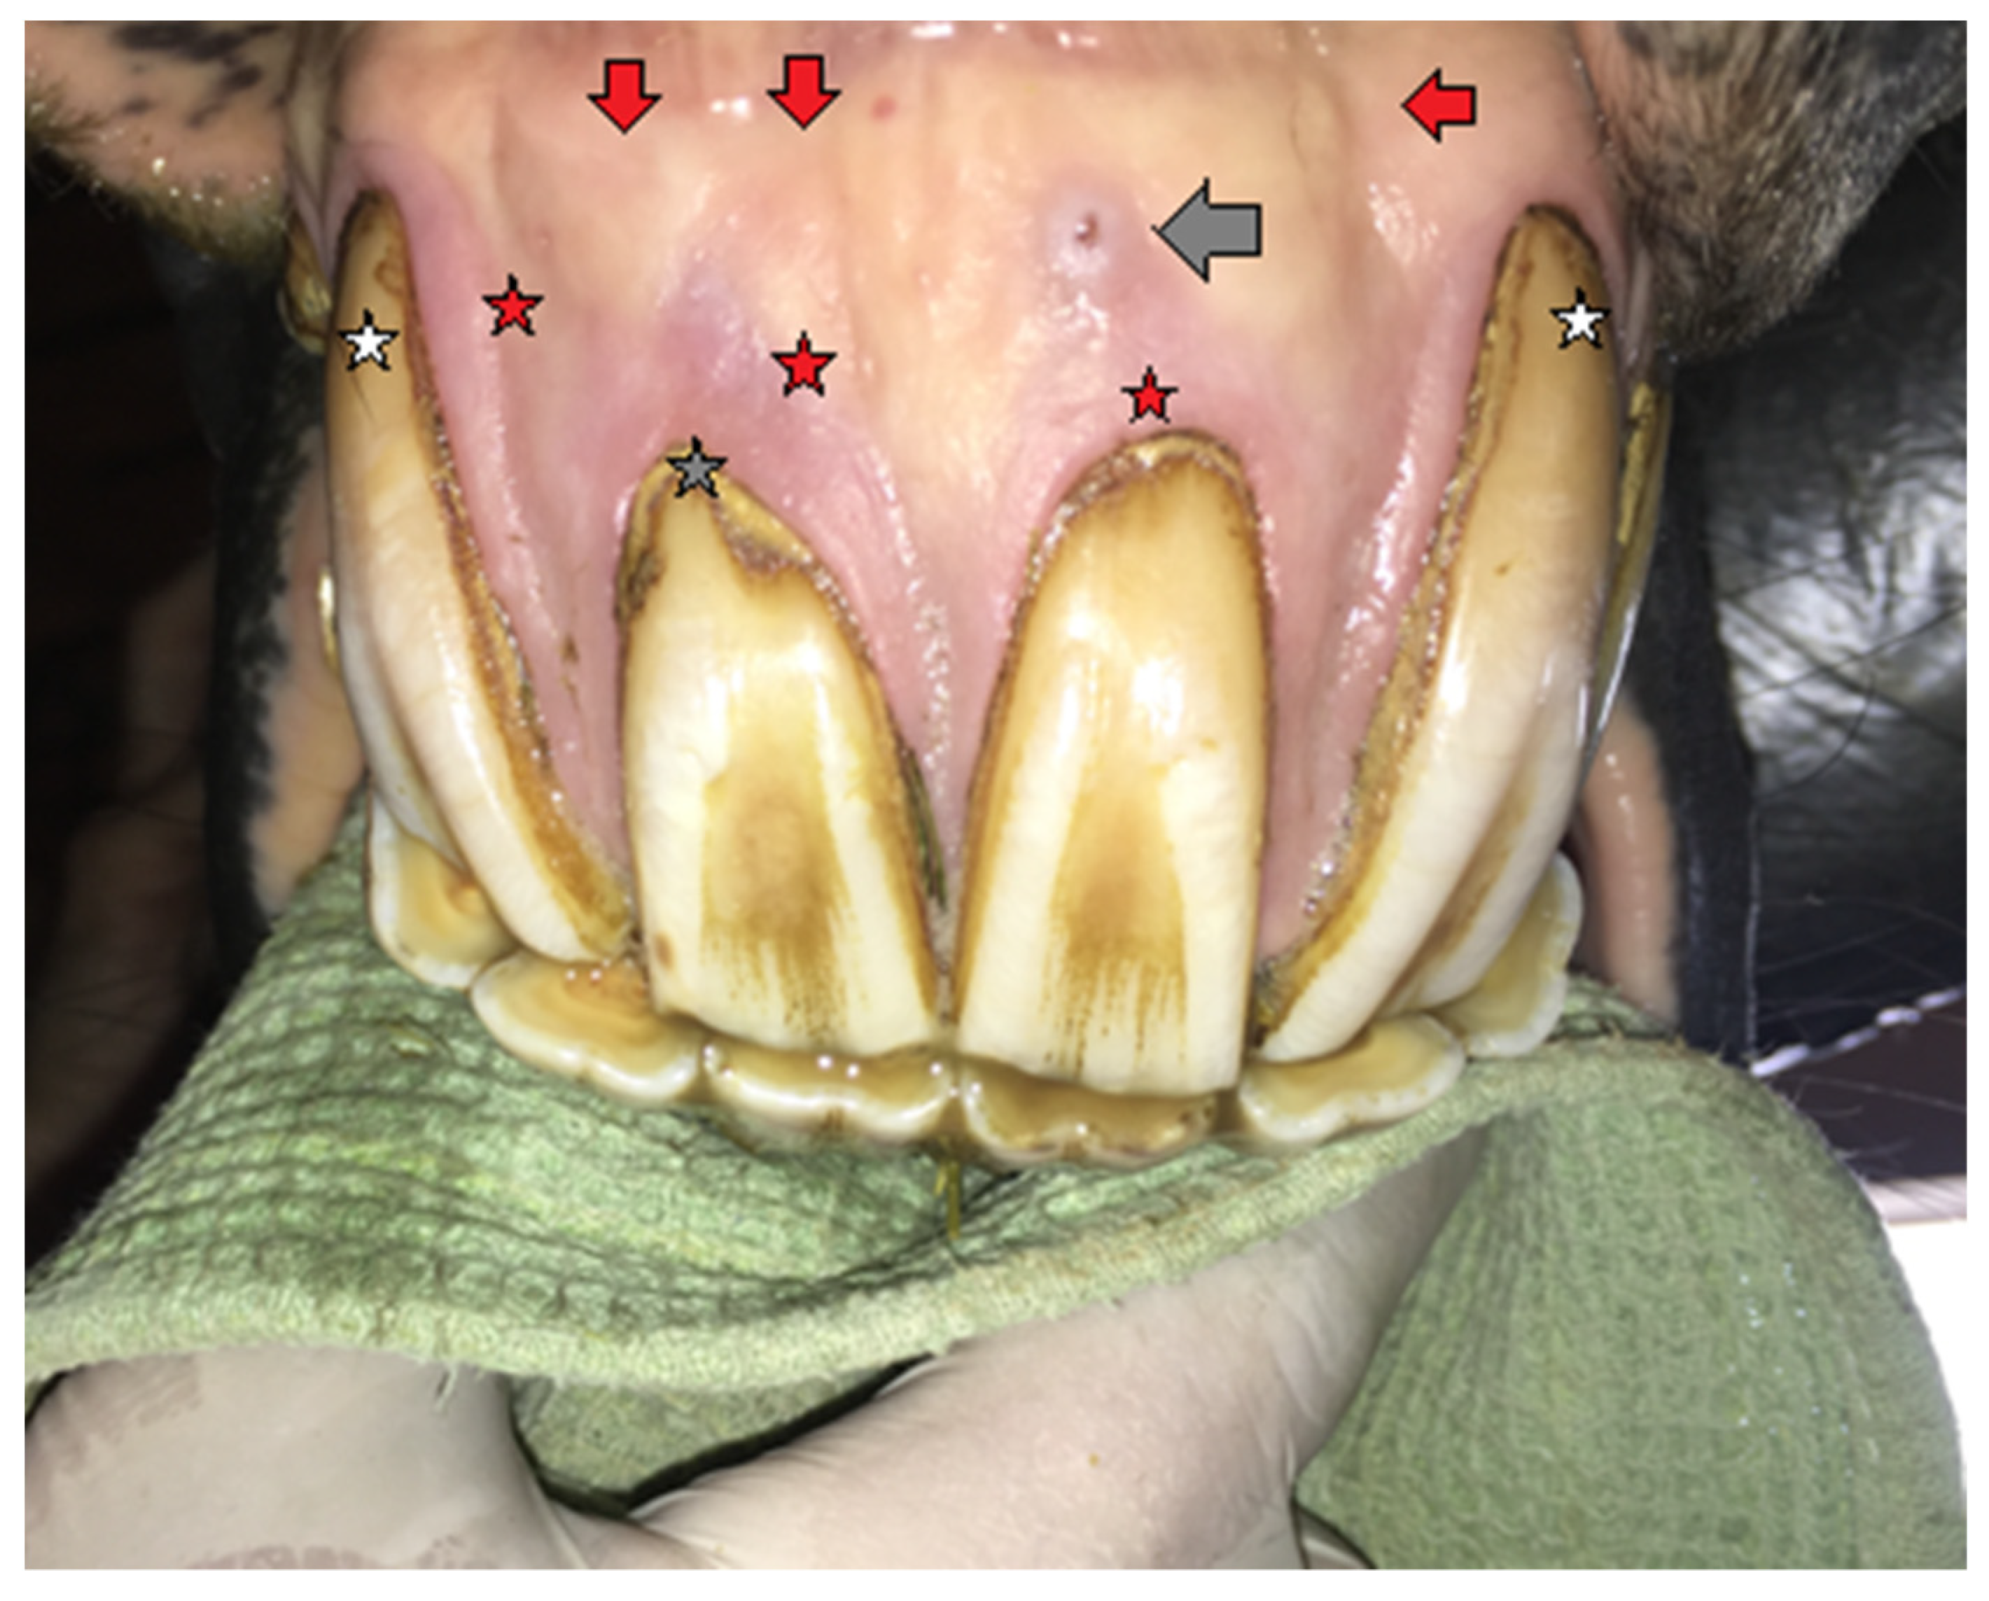

2.1.1. Case 1

2.1.2. Case 2